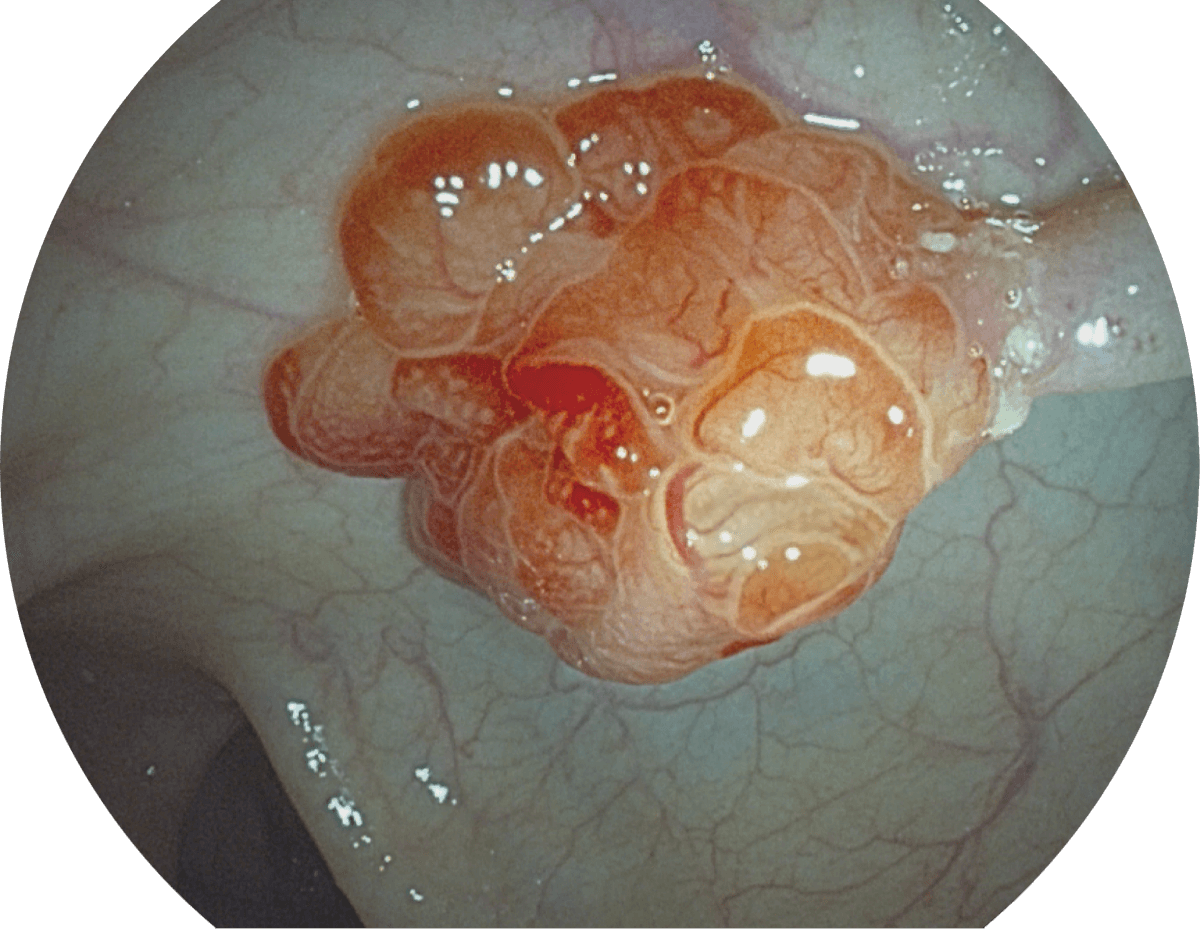

具有聚谱成像技术(SFI)及光电复合染色成像技术(VIST),可完美呈现粘膜细节及病变特征。

WL

SFI

VIST